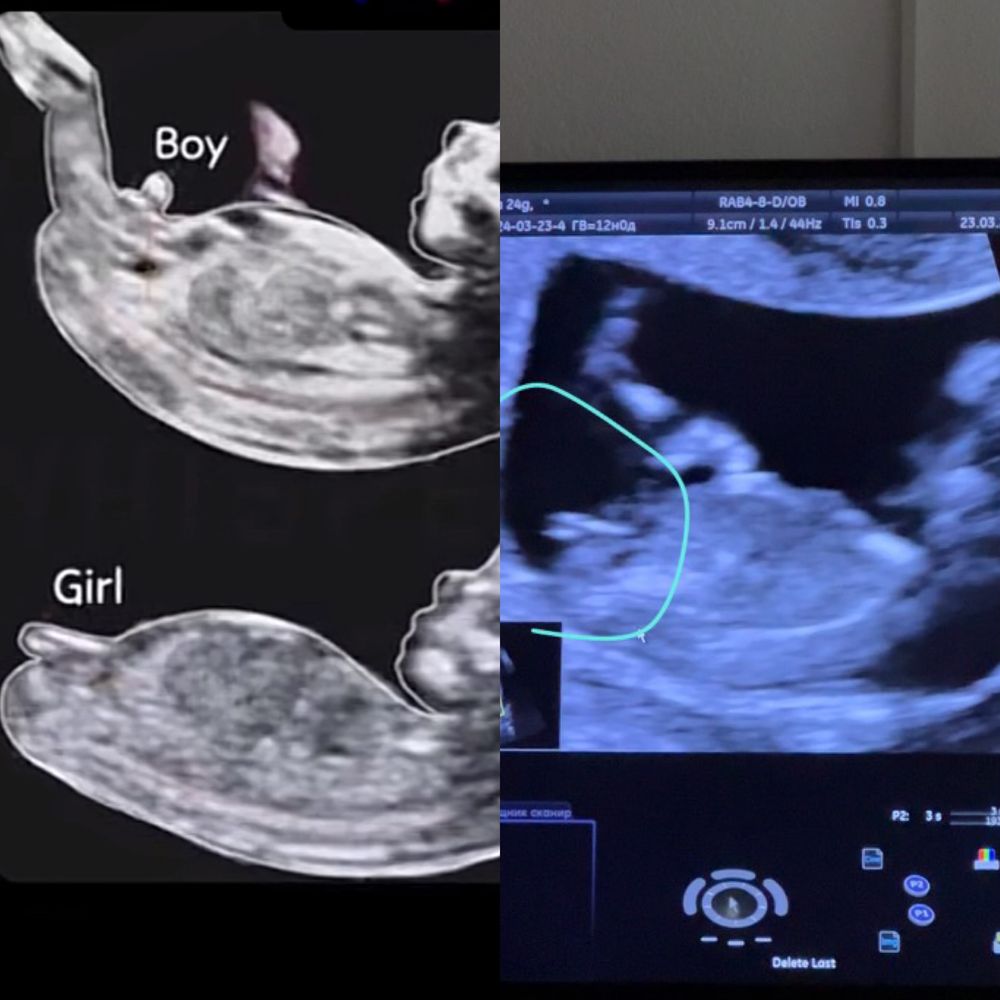

1 СКРИНИНГ ❤️ девчонка 80% носик мой☺️

Vale ria, я тоже по этому примеру смотрела и всё совпало. Хотя врач пол не сказал. Я сама выяснила 🤣

Dina, на этом сроке еще ни "яек" ни "писюна" нет, есть только половой бугорок. Пол определяется по его наклону. Здесь явно девочка.